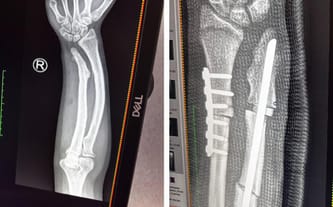

W grudniu informowałam Was o kolejnej operacji zaplanowanej na 6 lutego. Na szczęście odbyła się w terminie. Podczas zabiegu lekarze usunęli wcześniej założony gwóźdź, który nie spełnił swojej funkcji oraz założyli płytkę stabilizującą kość. Dodatkowo pobrano fragment kości z okolicy łokcia i przeszczepiono go w miejsce, w którym od dłuższego czasu nie dochodziło do zrostu kostnego.

Podczas wcześniejszej operacji lekarze założyli płytkę na jedną kość oraz śrubę na drugą, jednak po zdjęciu gipsu okazało się, że śruba w okolicy łokcia blokuje wyprost ręki. Dodatkowo w tym miejscu kość od trzech miesięcy w ogóle się nie zrasta.

Na co dzień córka zmaga się z bólem i ograniczoną ruchomością ręki, co bardzo utrudnia jej funkcjonowanie, naukę oraz rehabilitację. Największym uciążeniem jest brak możliwości normalnego używania prawej ręki i ciągły dyskomfort. Lekarze zdecydowali o konieczności kolejnej, pilnej operacji zaplanowanej na 6 lutego – śruba zostanie usunięta i zastąpiona płytką, aby umożliwić prawidłowe zrastanie kości.